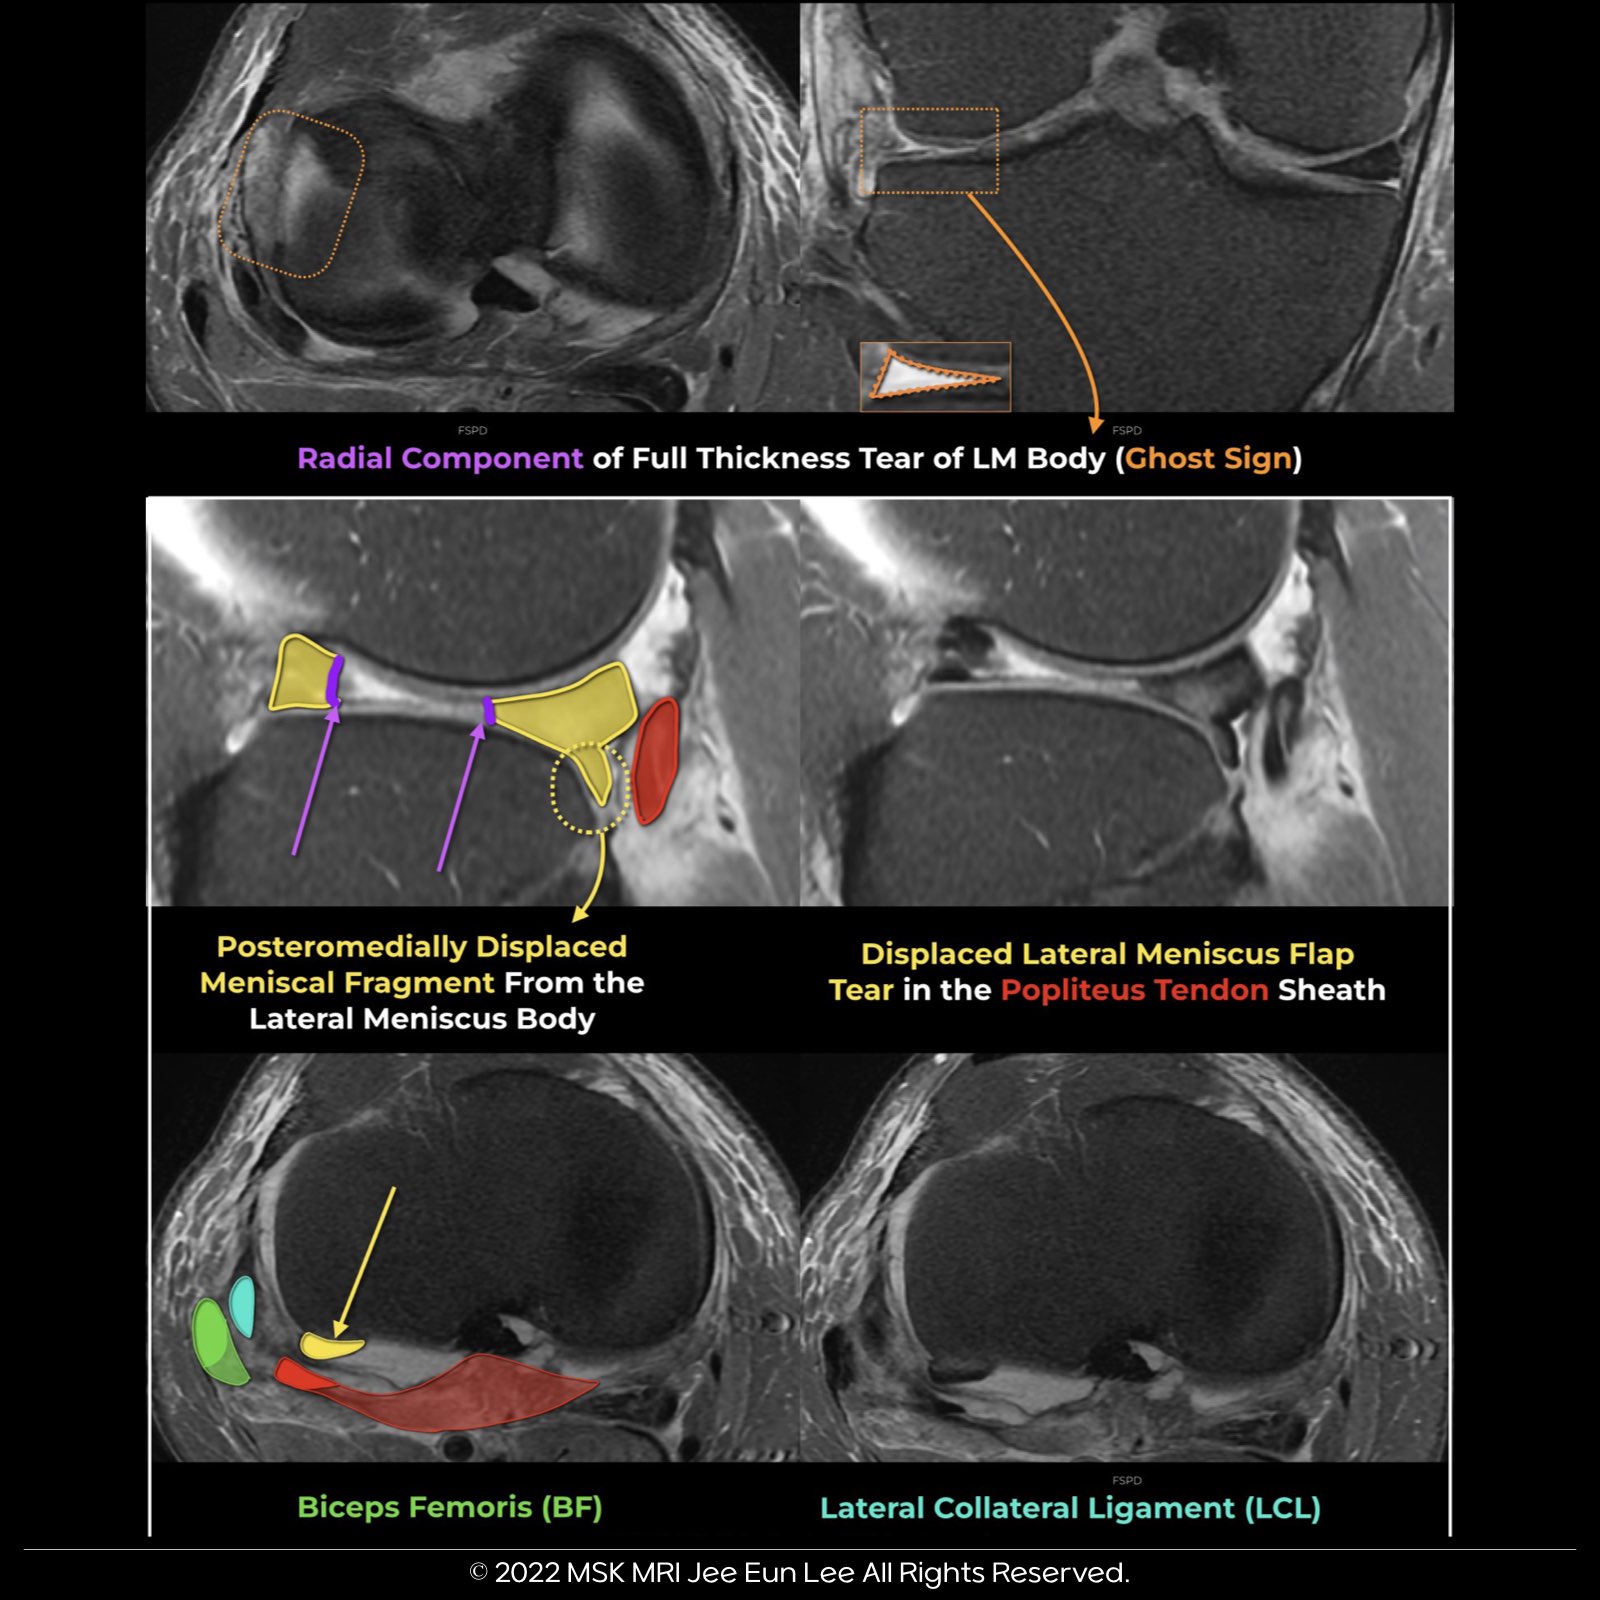

- This case isn't just a full-thickness radial tear. It's a displaced flap tear, with a trajectory moving posteromedially due to a tear in the body of the lateral meniscus.

- Originating from the lateral meniscus's body, the flap tear shifts posteromedially.

- Interestingly, we see a horizontal flap tear that has flipped posteriorly into the popliteus hiatus.

- The popliteus tendon sheath might provide a potential space for the displaced lateral meniscus flap tear.

- The displaced flap tear fragment is noticeable inferior to the lateral joint line and anterior to the popliteus tendon.